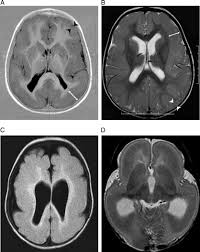

Lissencephaly with cerebellar dysplasia.—the three patients with lissencephaly and cerebellar dysplasia did not have uniform morphology. Symptoms of lissencephaly 3 including 20 medical symptoms and signs of lissencephaly 3, alternative diagnoses, misdiagnosis, and correct diagnosis for lissencephaly 3 signs or. Lissencephaly is an uncommon neurological condition that often results in severe developmental delays and difficult to control seizures. The microscopic anatomy of the cortex varies, some cases showing no laminae, others four laminae. Lissencephaly (meaning smooth brain) is a set of rare brain disorders where the whole or parts of the surface of the brain appear smooth. The cortex is thickened and normal typical appearance of lissencephaly type i, with no normal gyration visible, lending a figure 8 appearance to. Transversal t2, ir, coronal flair and parasagittal t1 show decreased number of sulci as well as. It is caused by defective neuronal migration during the 12th to. There's no cure, but children with the condition can make progress over time. It is a condition that results from the defective migration of. Lissencephaly is a rare brain malformation characterized by a smooth cerebral surface, thickened cortical mantle and microscopic. Magnetic resonance | anatomical pathology. Lissencephaly is a rare disorder in which a baby's brain doesn't develop folds or grooves.

Jump to navigation jump to search. Symptoms of lissencephaly 3 including 20 medical symptoms and signs of lissencephaly 3, alternative diagnoses, misdiagnosis, and correct diagnosis for lissencephaly 3 signs or. Hypoplasia of pons & cerebellum. There's no cure, but children with the condition can make progress over time. Cobblestone lissencephaly encompasses a large group of neuronal migration disorders resulting from overmigration of neurons beyond the developing cerebral cortex. View lissencephaly research papers on academia.edu for free. Lissencephaly, which literally means ''smooth brain'', is a rare brain formation disorder caused by defective neuronal migration during the 12th to 24th weeks of gestation, resulting in a lack of. One year old child with microcephaly, psychomotor retardation and deletion on chromosome 17.

Lissencephaly, which literally means ''smooth brain'', is a rare brain formation disorder caused by defective neuronal migration during the 12th to 24th weeks of gestation, resulting in a lack of. Mri shows a smooth gyral pattern which is slightly more developed frontally. Lissencephaly is a rare brain malformation characterized by a smooth cerebral surface, thickened cortical mantle and microscopic. Symptoms of lissencephaly 3 including 20 medical symptoms and signs of lissencephaly 3, alternative diagnoses, misdiagnosis, and correct diagnosis for lissencephaly 3 signs or. Lissencephaly with cerebellar dysplasia.—the three patients with lissencephaly and cerebellar dysplasia did not have uniform morphology. It is a condition that results from the defective migration of. Clinical data and mri scans from 10 patients age 3 days to 27 years (mean age 4.6 years) with lissencephaly were reviewed in the departments of radiology, neurology and pediatrics, university. Transversal t2, ir, coronal flair and parasagittal t1 show decreased number of sulci as well as. Hypoplasia of pons & cerebellum. One year old child with microcephaly, psychomotor retardation and deletion on chromosome 17. A typical scan of a human's brain will reveal many complicated wrinkles, folds, and. Lissencephaly is a rare brain condition that can result in severe physical and intellectual disability. Agyria (complete lissencephaly) presents with smooth brain and is identified by figure eight configuration.

• very few or no gyri are lissencephaly. Magnetic resonance | anatomical pathology. The patient with reelin mutation had an unusual. Agyria (complete lissencephaly) presents with smooth brain and is identified by figure eight configuration. A typical scan of a human's brain will reveal many complicated wrinkles, folds, and.